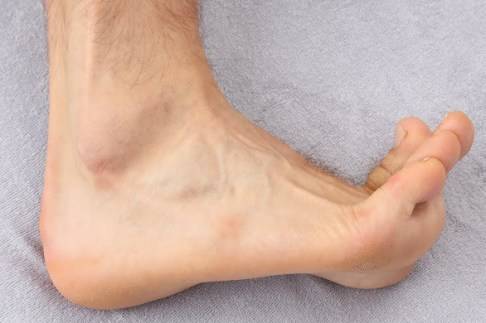

Als schmerzbedingte Schonhaltung gehen Patienten mit Fersenschmerzen oft verstärkt über den Fußaußenrand. Diese Ausweichbewegung kann zu einem seitlichen Schmerz an der Ferse und zu Schmerzen im Unterschenkel führen.

Der Knick-Senkfuß betrifft im Erwachsenenalter häufig Frauen und hat oft eine Schwäche der vom Unterschenkel in den Fuß ziehenden Bänder, insbesondere der Tibialis-posterior-Sehne, zur Ursache. In der Folge sinkt das Fußgewölbe ab und die Ferse kippt nach außen ab. Diese Fußfehlstellung verlagert die herrschenden Zugkräfte gravierend und kann langfristig zu Plantarsehnenentzündung und Fersensporn führen.